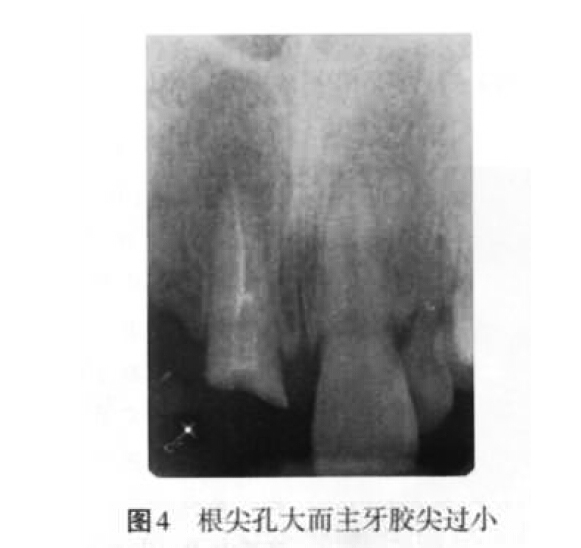

(2)超充原因:主要包括預(yù)備成形不良、根尖孔大而主牙膠尖過(guò)?。▓D4)、根管工作長(zhǎng)度測(cè)量不準(zhǔn)確、根充技術(shù)選擇不當(dāng)以及術(shù)者操作不當(dāng)?shù)仍颉?/p>